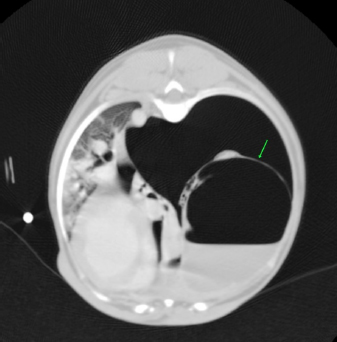

No complication due to ABP was observed. Control thoracic X-rays were obtained 24 hours and 1 week after the procedures, which did not show any signs of relapse in dogs 1 through to 4 (Fig. 4).

Fig. 4. Right-lateral thoracic radiographic of the same dog in Figure 3, 24 hours after autologous blood patch pleurodesis.